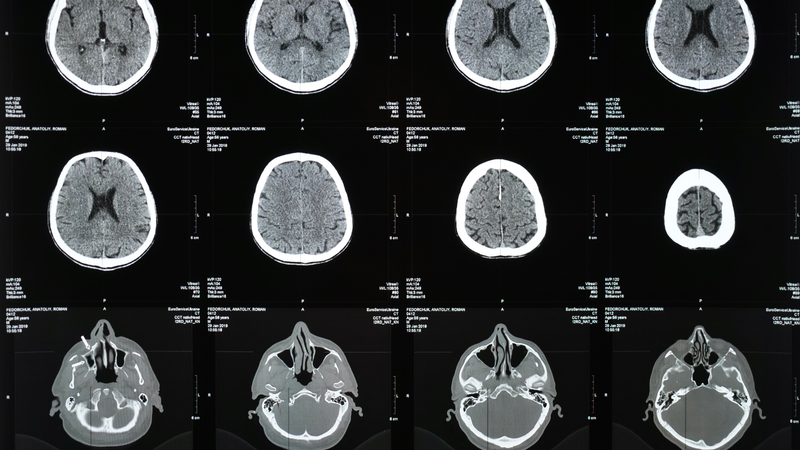

Đột quỵ là một trong những nguyên nhân hàng đầu gây tử vong và tàn tật trên toàn thế giới. Việc chẩn đoán sớm và chính xác các tổn thương não là yếu tố then chốt trong việc cải thiện hiệu quả phục hồi chức năng sau đột quỵ. Trong những năm gần đây, các kỹ thuật chụp ảnh não tiên tiến đã mở ra nhiều hy vọng mới trong việc phục hồi cho bệnh nhân đột quỵ.

Trong một bước tiến quan trọng trong lĩnh vực phục hồi sau đột quỵ, Trung tâm Y khoa Đại học Georgetown đã hợp tác cùng MedStar Health và Viện Y tế Quốc gia (NIH) để tiến hành nghiên cứu về kỹ thuật hình ảnh não mới. Nghiên cứu này hứa hẹn mang lại những thông tin chi tiết hơn về tình trạng của các đường dẫn chất trắng, từ đó giúp tùy chỉnh phương pháp phục hồi cho bệnh nhân bị đột quỵ.

Các nhà khoa học tại Trung tâm Y khoa đại diện bởi Edwardson và các đồng nghiệp đã phát hiện ra rằng việc kết hợp kỹ thuật MRI truyền thống với một phương pháp mới gọi là hình thái dựa trên khuếch tán tensor (DTBM) có thể cung cấp hình ảnh chi tiết hơn về các đường dẫn chất trắng đến chi. Kỹ thuật này giúp xác định liệu các cáp này có bị suy teo hay không, một thông tin quý giá để đánh giá khả năng hồi phục sau đột quỵ của bệnh nhân.

DTBM là một kỹ thuật tiên tiến kết hợp thông tin định hướng với hình dạng và kích thước của các cấu trúc não được hình ảnh hóa. Trước đây, các nhà thần kinh học thường gặp khó khăn trong việc phân biệt các cáp chất trắng từ chất xám bằng cách sử dụng các phương pháp hình thái thông thường. Tuy nhiên, với sự ra đời của DTBM, các nhà nghiên cứu có thể lập bản đồ và định lượng các thay đổi theo thời gian trong các đường dẫn chất trắng.